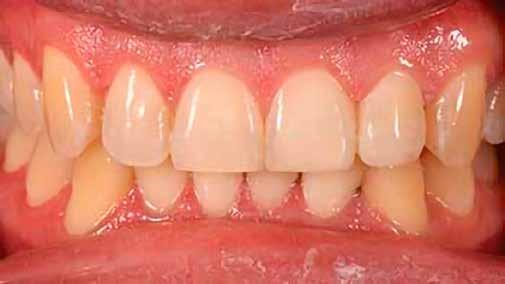

12. ábra: A premoláris fogak preoperatív állapota.

13. ábra: A premoláris fogak postoperatív fotója.